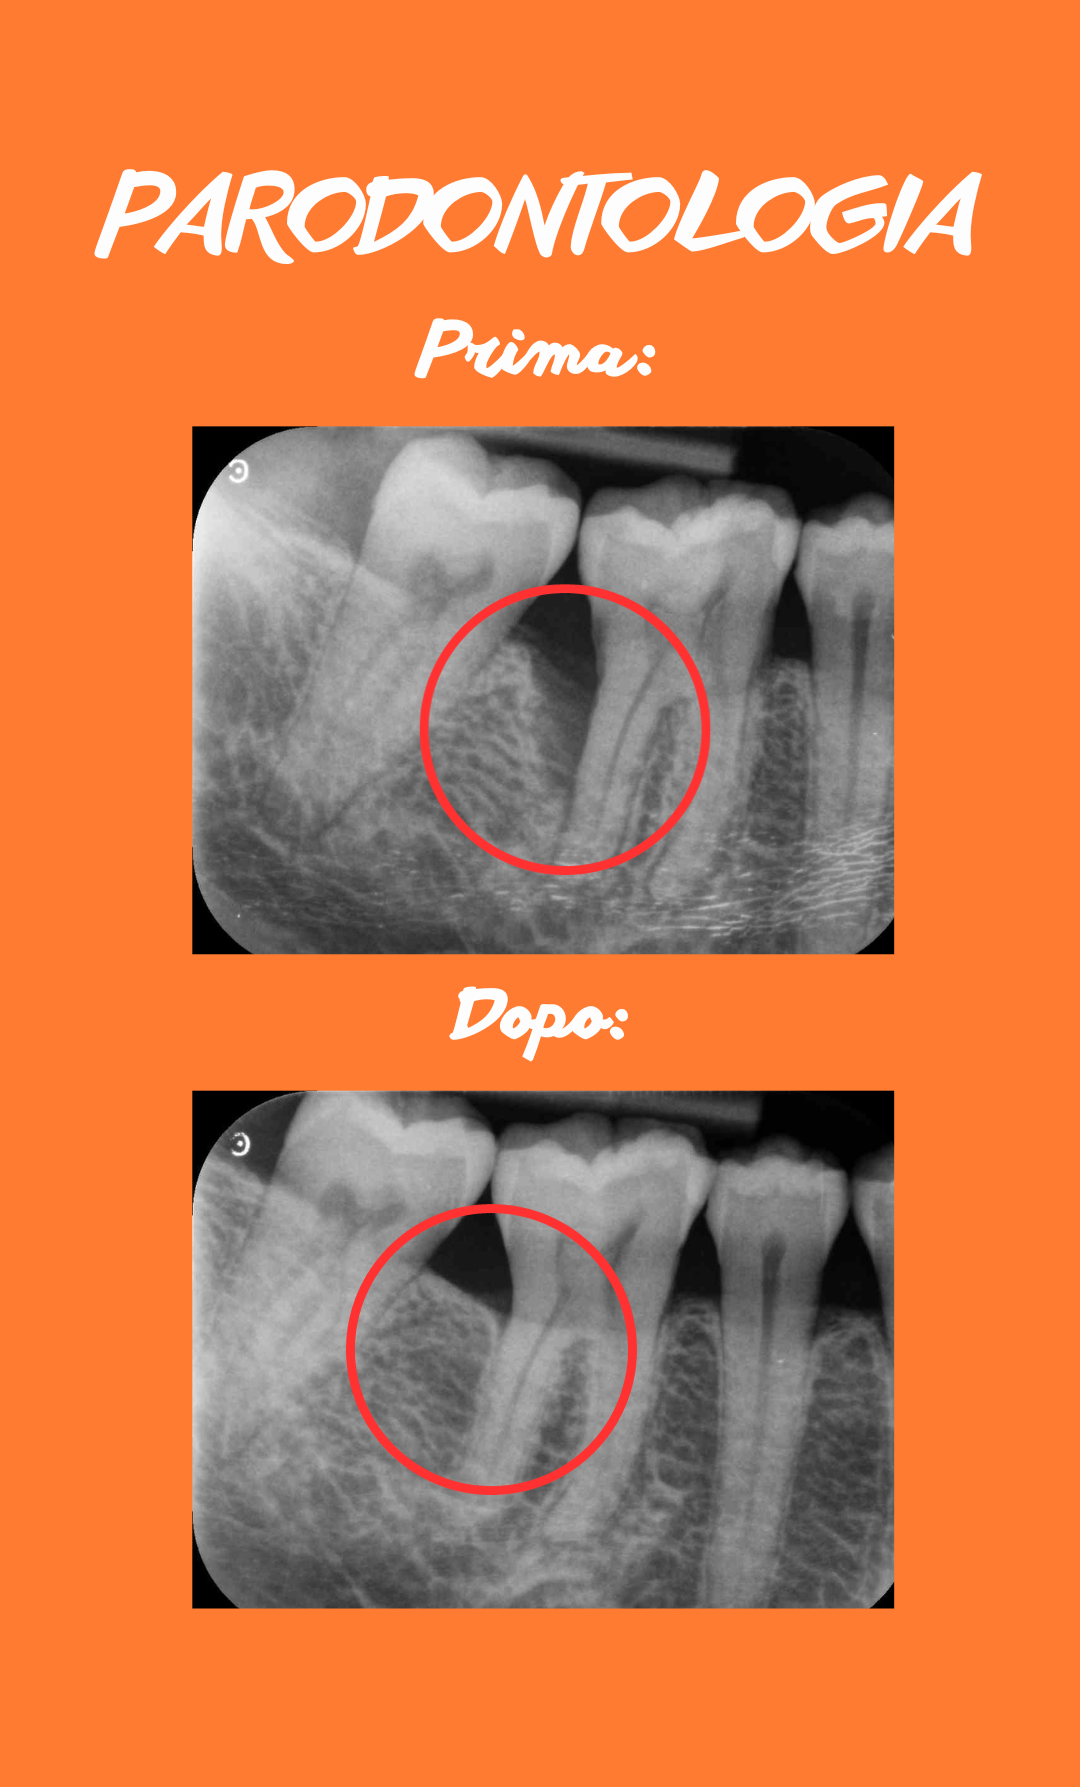

Parodontologia: riferimento per la gestione dei casi parodontali complessi

La parodontologia è la disciplina odontoiatrica che si occupa della prevenzione, diagnosi e trattamento delle patologie che interessano i tessuti di supporto del dente, come gengive, osso e legamento parodontale. Negli ultimi anni, lo Studio Odontoiatrico del Dr. Alessandro Bermond Des Ambrois, un’eccellenza riconosciuta nella parodontologia sul territorio, è diventato un punto di riferimento per il trattamento dei casi parodontali, sia nelle forme iniziali sia in quelle più complesse, grazie a un approccio clinico strutturato e all’utilizzo di protocolli aggiornati. All’interno dello studio, l’approccio parodontale è fortemente orientato all’individuazione precoce di condizioni infiammatorie o degenerative, come gengiviti e parodontiti, che nel tempo possono compromettere la stabilità dei denti naturali e la salute generale del cavo orale.

Il trattamento parodontale viene pianificato a partire da una valutazione clinica approfondita, supportata da strumenti diagnostici dedicati che consentono di definire con precisione il quadro clinico del paziente. L’obiettivo è controllare l’infiammazione, preservare i tessuti di sostegno e mantenere la funzionalità dell’apparato masticatorio, integrando la terapia con un percorso di prevenzione personalizzato e di educazione alla corretta igiene orale domiciliare. Questo approccio graduale e proporzionato permette di gestire la patologia in modo efficace nel tempo, favorendo il mantenimento della salute orale nel lungo periodo e migliorando la qualità di vita del paziente.